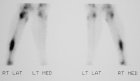

S.P. - 15 year old female presents with two month hx of right calf pain. Pain awakens her from sleep.